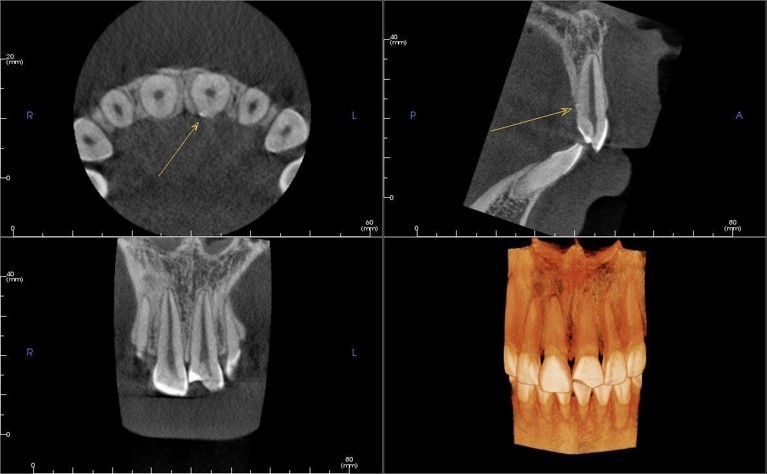

Рентгенологическое исследование

Формирование корня: ☑ Завершенное

Прицельные снимки и реформаты

КЛКТ после фиксации фрагмента зуба